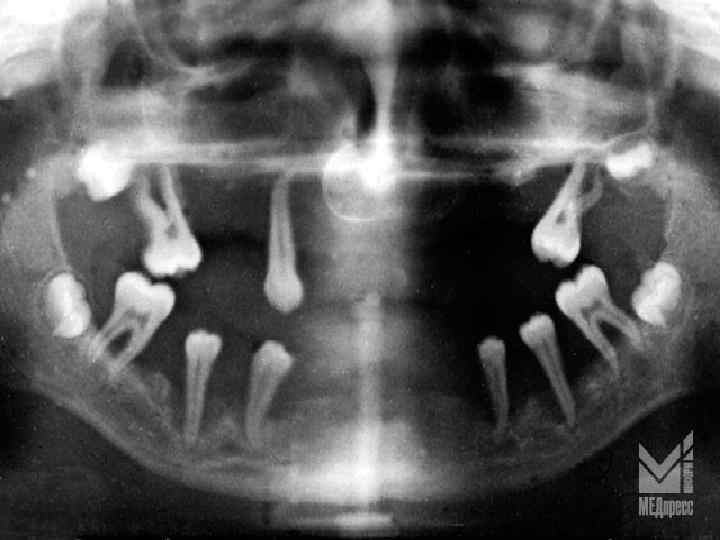

• 1, 5– 2 есеге иммунорегуляторлы индекстің тұрақты төмендеуі (Т-лимфоциттердің хелперлік және супрессорлық популяцияларының арақатынастарының бұзылуы), нәтижесінде пародонт қабынуының бұл түрінде ем нәтижесіз болады. • рентгенологиялық зерттеулерде (ортопантомография) қабынулы деструктивті процесстің белсенділігін көрсететін альвеолярлы өсіндінің сүйек тінінің жайылмалы бұзылысы шекарасы анық емес остеопороздың ірі ошақтарын